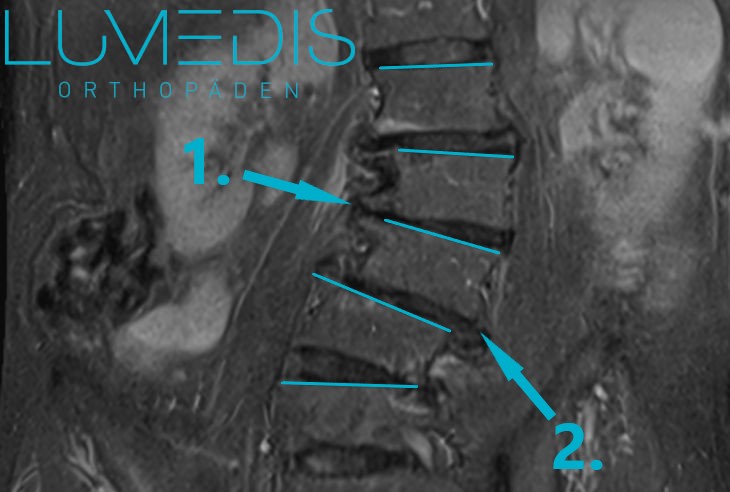

MRT der LWS / BWS mit schwerer Skoliose - über die Stellung der Deckplatten

Durch türkise Linien gekennzeichnet, kann man die Skoliose gut erkennen.